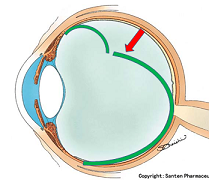

図の赤矢印の部分は視神経乳頭と言って、網膜が集まって束になる部分なのですが、実はこの部位のみ光を感じ取ることはできないのです。

マリオット盲点以外の部位が欠ける場合は病気となるのですが、視野が欠ける代表的な疾患として、緑内障があります(日本人の失明の原因の第一位)。

マリオット盲点を認識しづらいのと同様に、実は、緑内障で視野が欠けた場合も初期の段階では気が付きにくいのです。(初めて病院に来る時には、末期だったんてことがよくあります。)